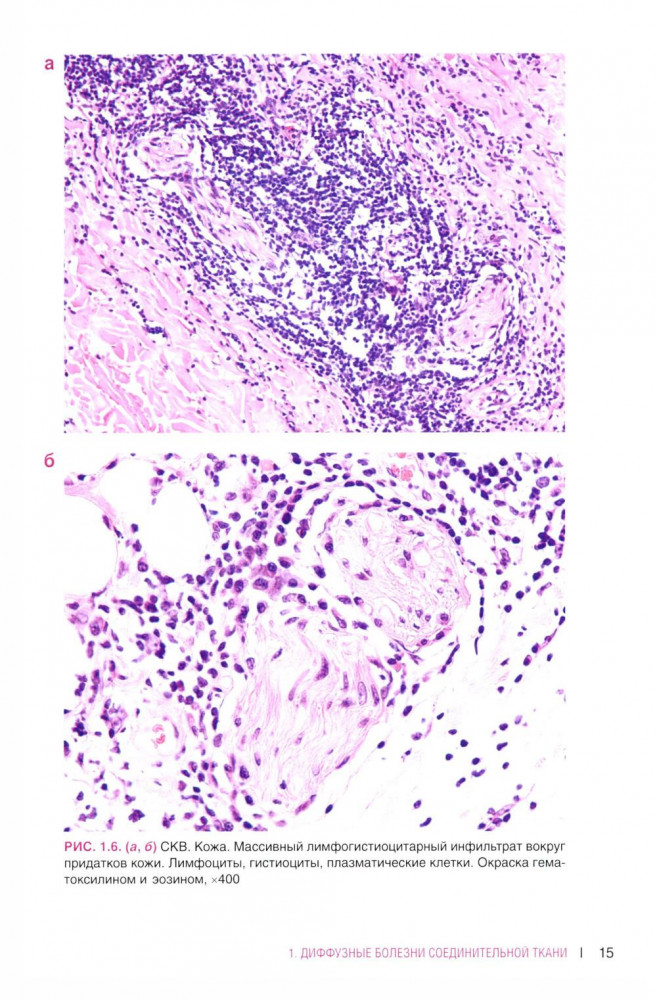

💳 Оплатить за товар можно при получении 🇰🇿 Есть бесплатная доставка по Казахстану от 1 дня 🎁 Копите бонусы с каждой покупки В атласе представлены авторские гистологические иллюстрации различных ревматических заболеваний, включая ревматоидный артрит, системную красную волчанку, системную склеродермию. Включены некоторые редкие патологии, такие как склеро-микседема, lgG-ассоциированное заболевание, панникулиты, аутовоспалительный синдром, ассоциированный адъювантами. Широко представлены системные васкулиты. |